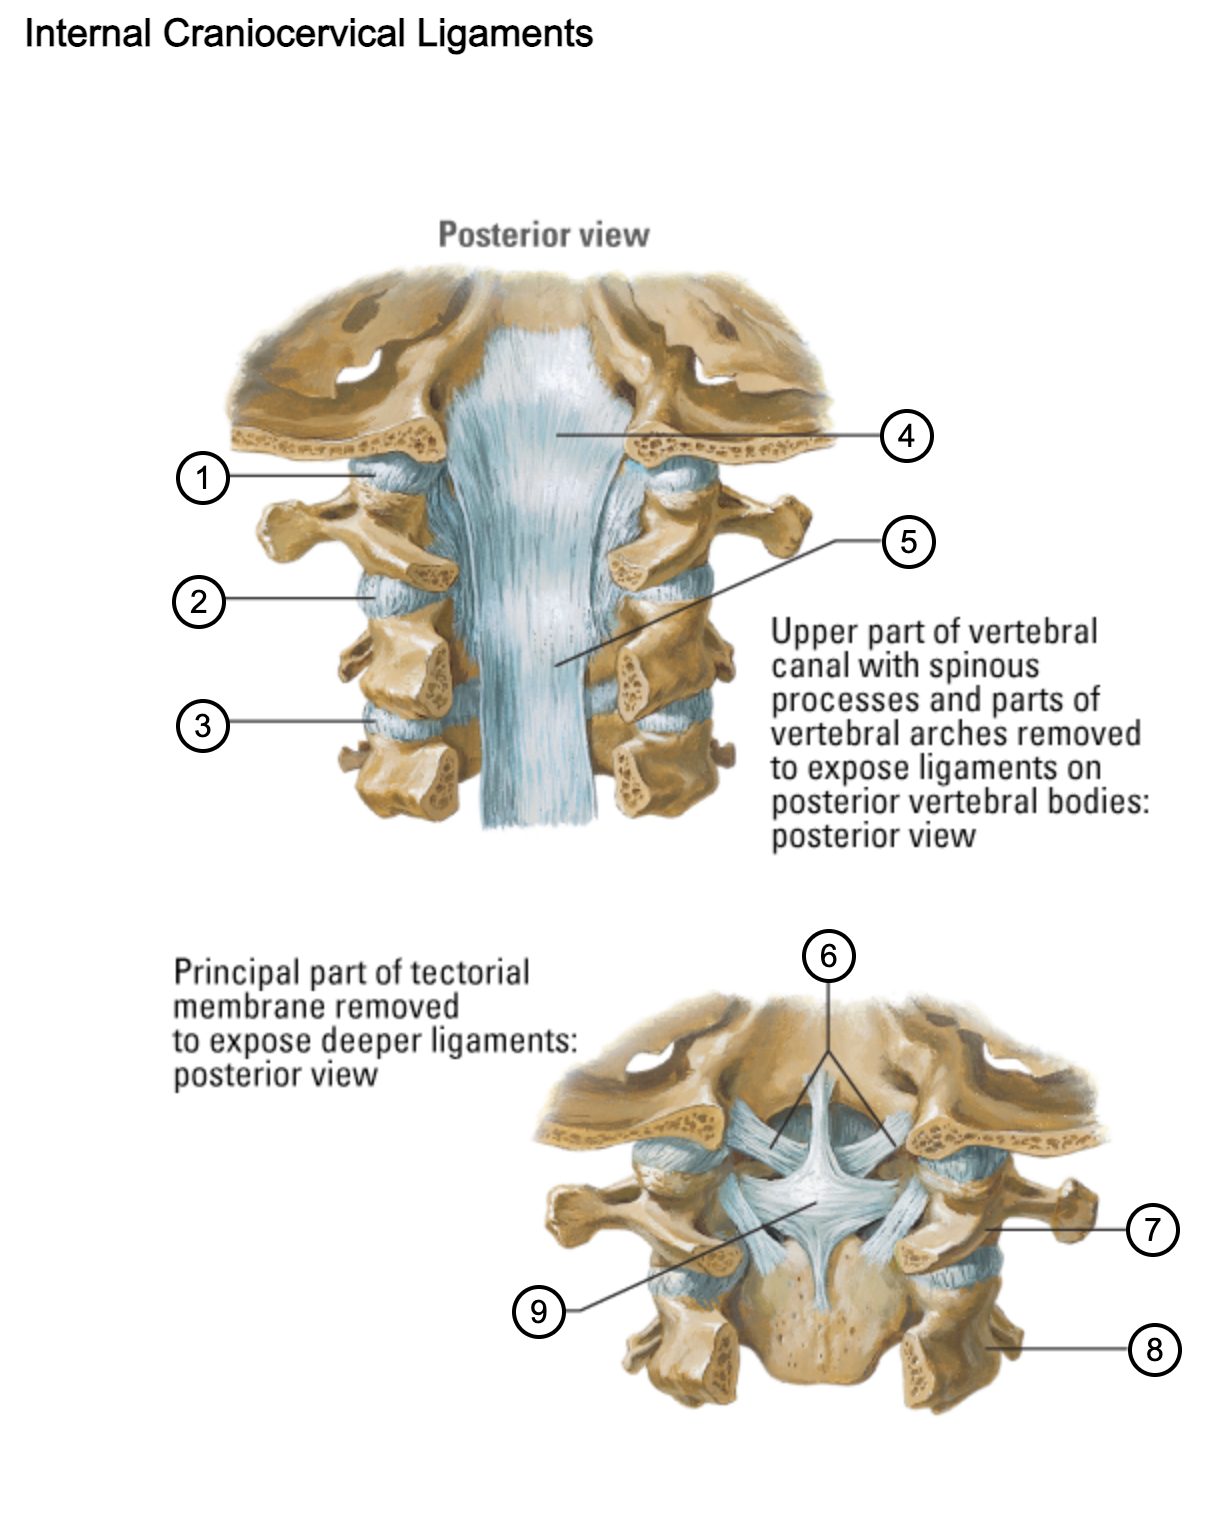

1

capsule of atlantooccipital joint

2

capsule of lateral atlantoaxial joint

3

capsule of zygapophysial joint (between axis and C3 vertebra)

4

tectorial membrane of cervical vertebral column

5

posterior longitudinal ligament

6

alar ligaments

7

atlas (C1)

8

axis (C2)

9

cruciform ligament (superior longitudinal band; transverse ligament of atlas; inferior longitudinal band)